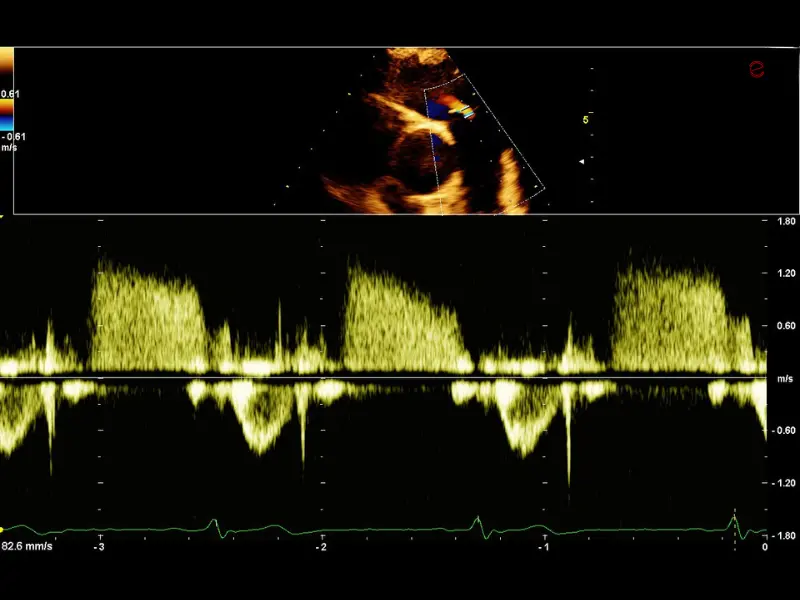

MyLab™C30 - Doppler - CW

MyLab™C30 - Doppler - CW